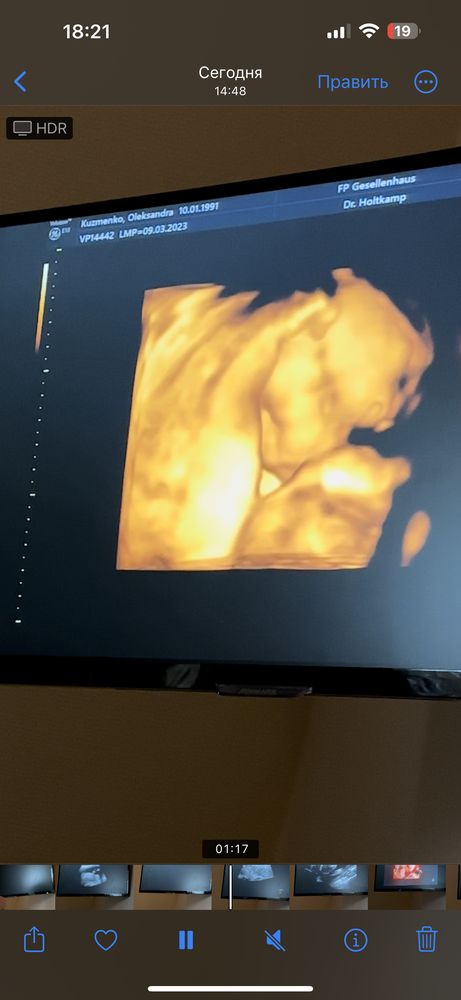

Неожиданный поворот при узи на 21-й неделе

ЭкваторСегодня был первый (второй) скрининг, срок 20.5. До этого дня очень переживала за малыша,почему то загоняла себя мыслями а вдруг что не так, всё таки возраст, который в группе риска. Но

к счастью всё в полном порядке. Опережаем почти на две недели (по замерам),вес 473 грамма. Ну и собственно сам нежданчик в том , что ждали ДОЧЬ, а дождёмся СЫНА😄 Узи делали каждые две-три недели и каждый раз мне подтверждали девочку, но сегодня я пошла к другому врачу, аппарат там шикарный был, там меня и огорошили😄. Но я не расстроилась, мне важно здоровье карапуза!) Для малыша уже давно всё куплено и в нейтральных цветах, так что слава богу менять не прийдется))Много таких историй слышала но не думала что сама с этим столкнусь😄